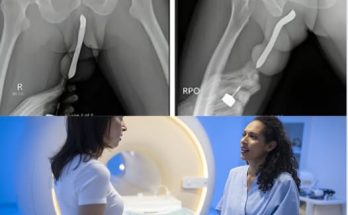

Young man hospitalized because he dropped his ca…See more

Young man hospitalized because he dropped his ca…See more Read More